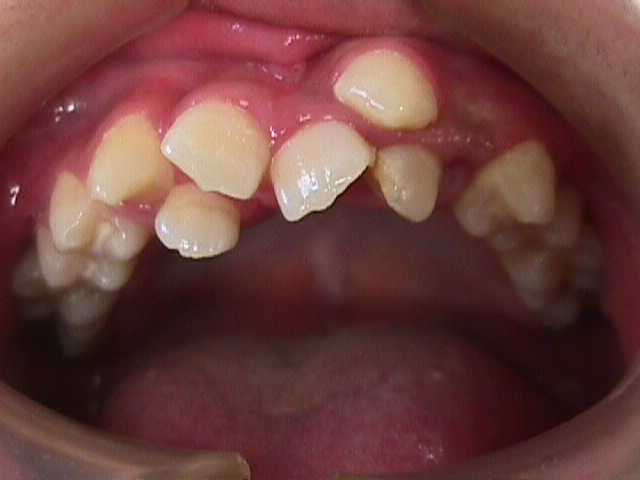

【矯正症例】左上2番3番逆転症例2

Before

左上2番3番逆転症例

随分、前の症例で現在、写真しか残っておりません。

治療費や、治療期間を掲載できないことをご了承ください。

私の矯正歯科医の人生の中でも、特に思い出深い症例です。